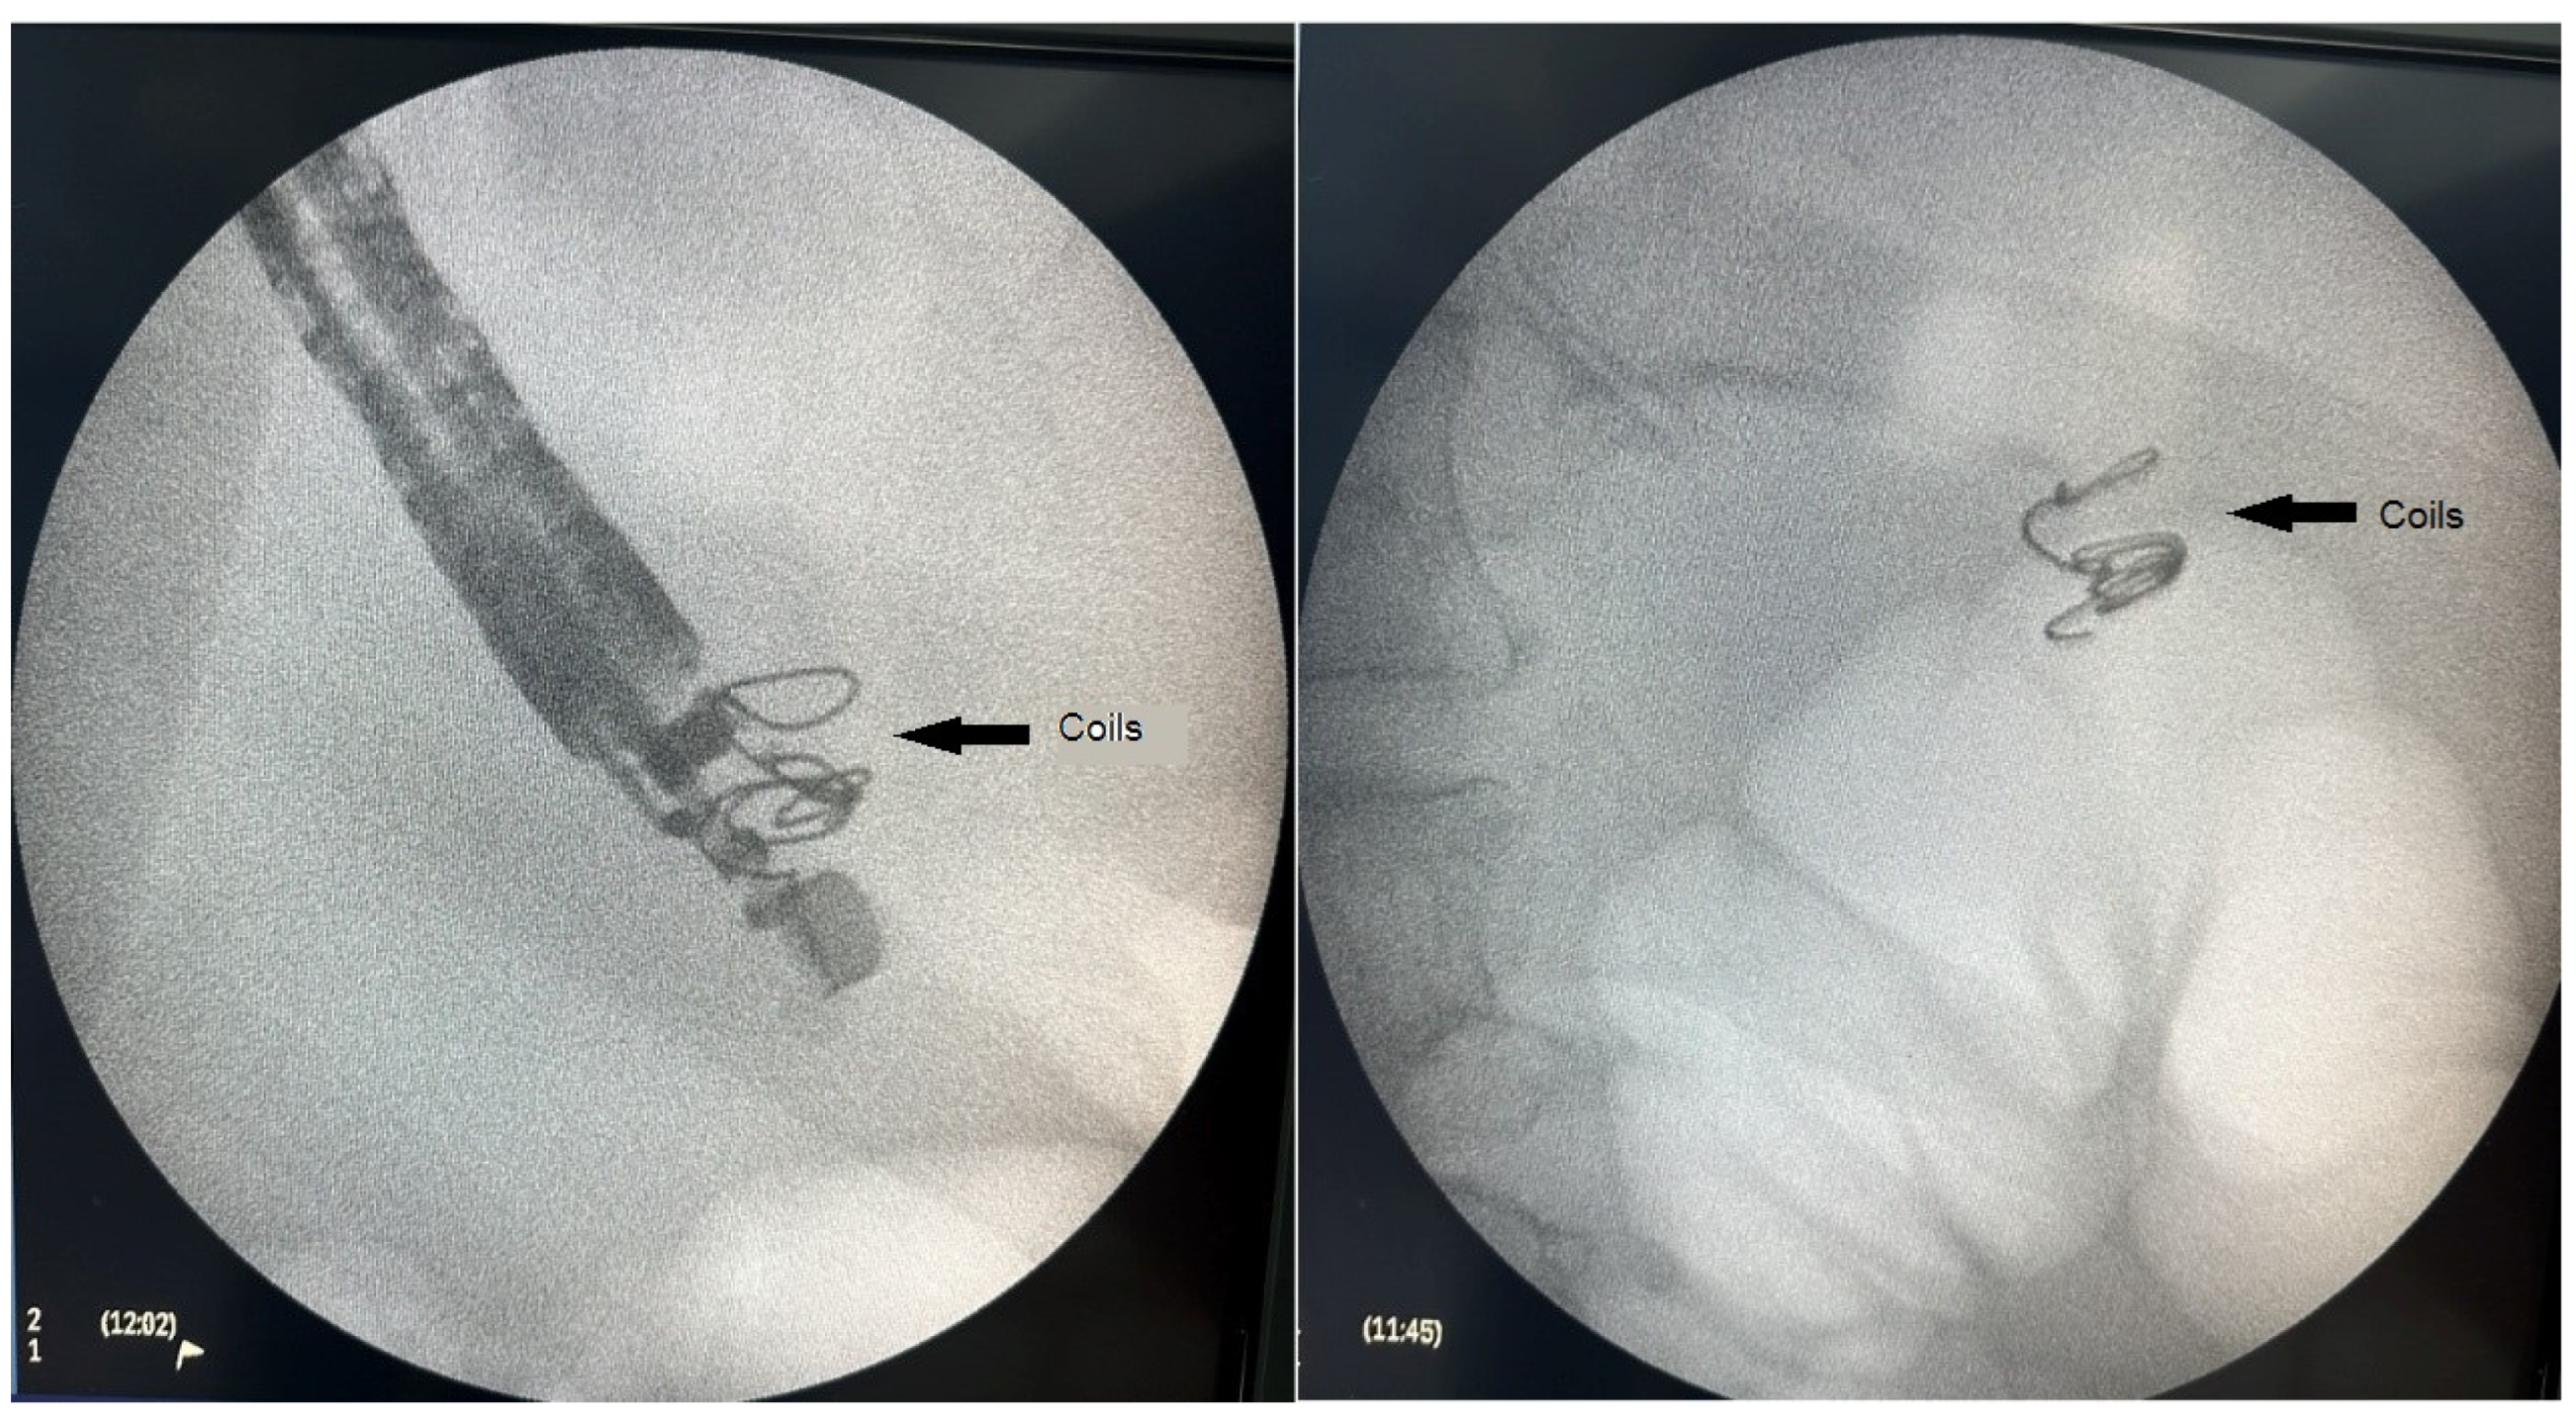

2.2. Technique Description